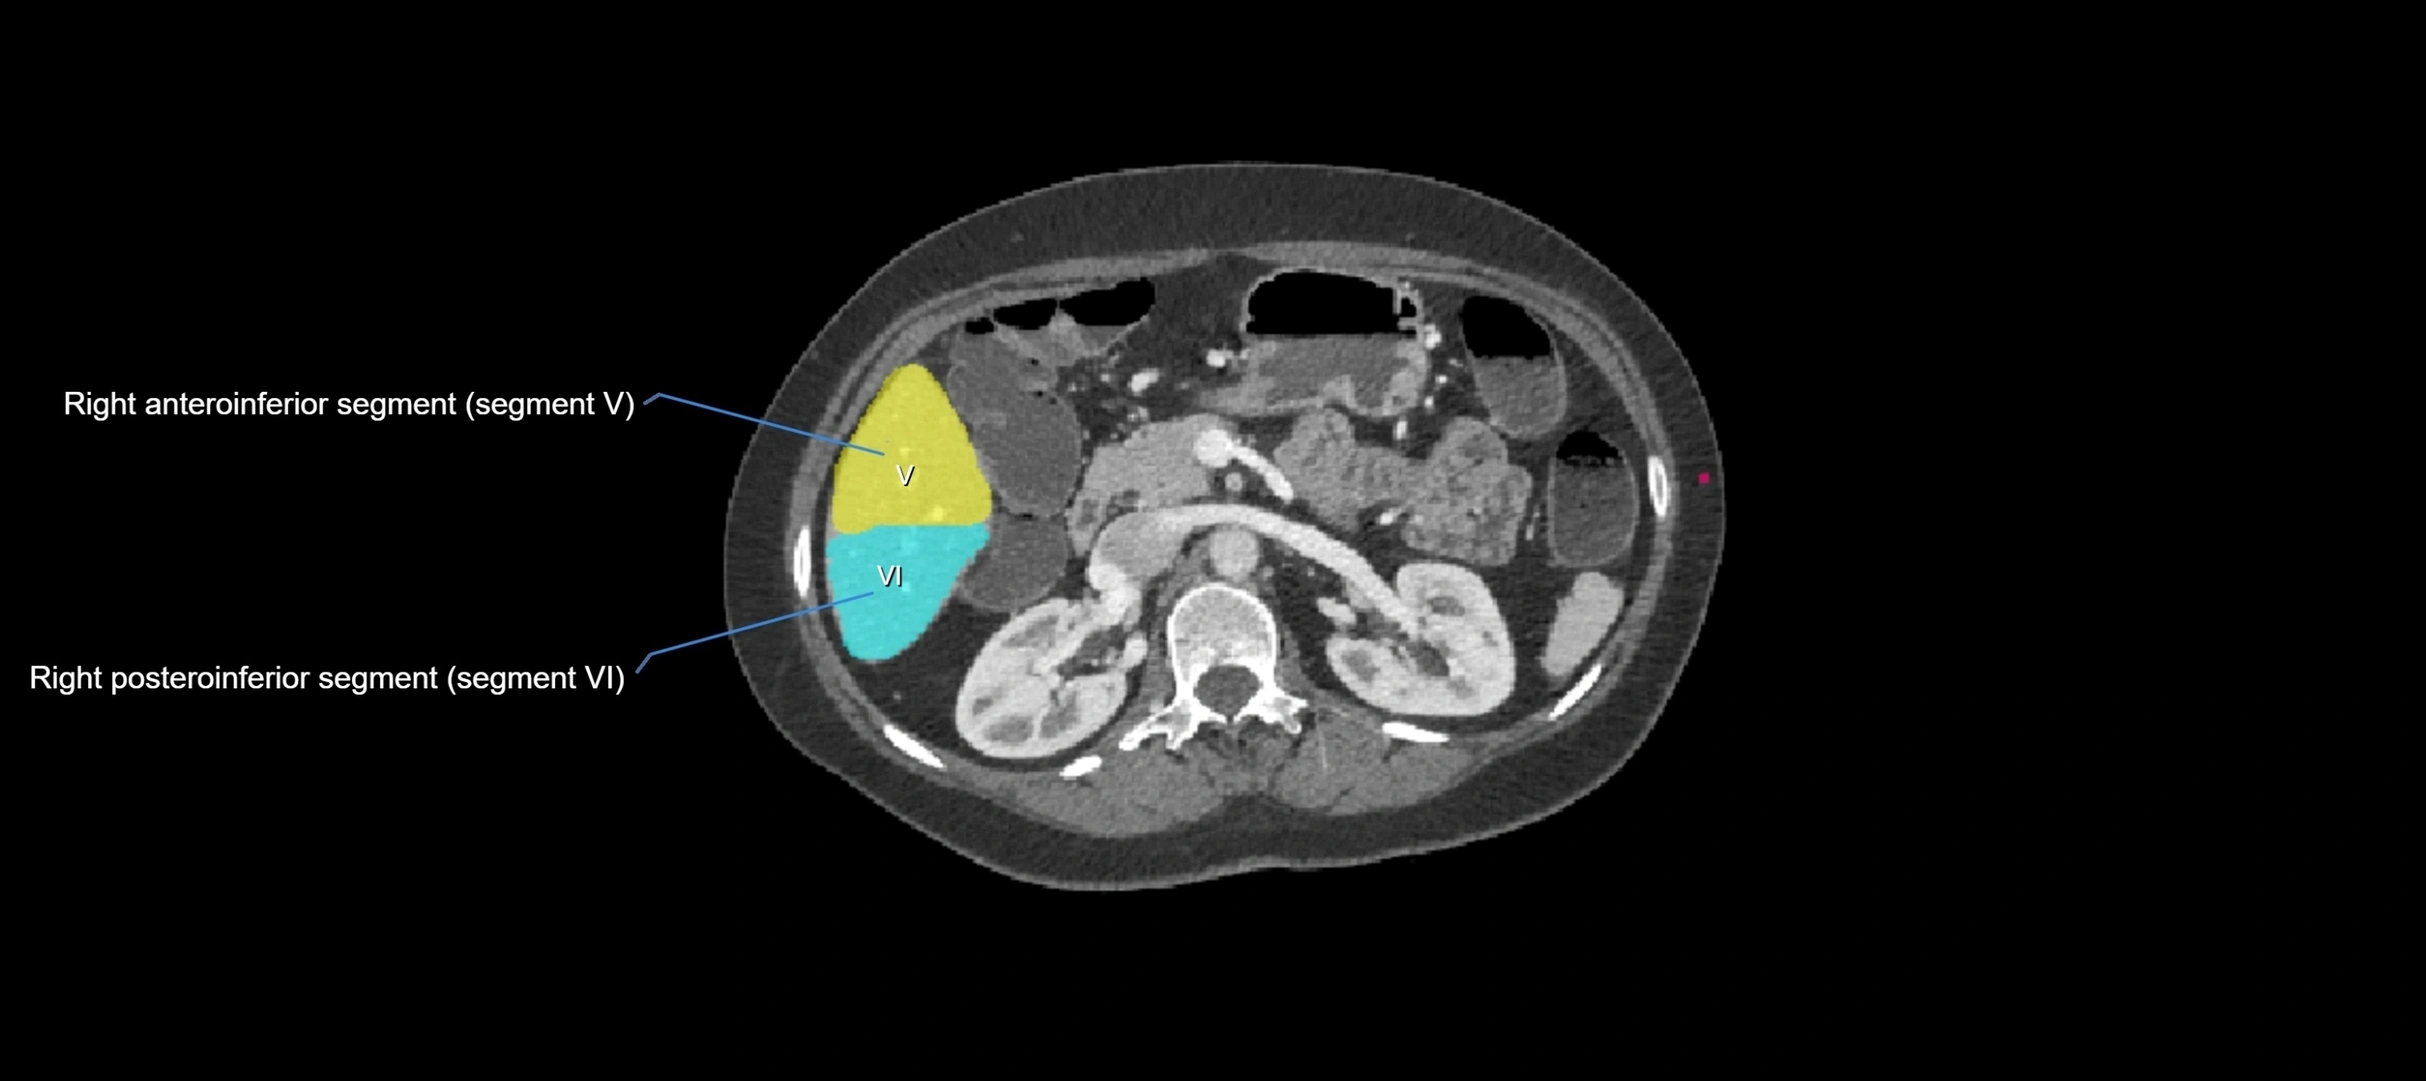

CT Appearance

CT Pre-Contrast:

• Caudate lobe appears as a soft-tissue density, isodense to the rest of the liver

• Enlargement may be appreciated in cirrhosis or Budd–Chiari syndrome

CT Post-Contrast:

• Homogeneous enhancement in the portal venous phase, similar to rest of liver

• Independent venous drainage into the IVC may be visualized

• Lesions follow characteristic CT enhancement patterns (HCC: arterial hyperenhancement with washout; hemangiomas: peripheral nodular enhancement with centripetal fill-in)

CT Venous Phase (functional significance):

• Caudate lobe often enhances relatively more than other lobes in Budd–Chiari syndrome, due to preserved venous outflow